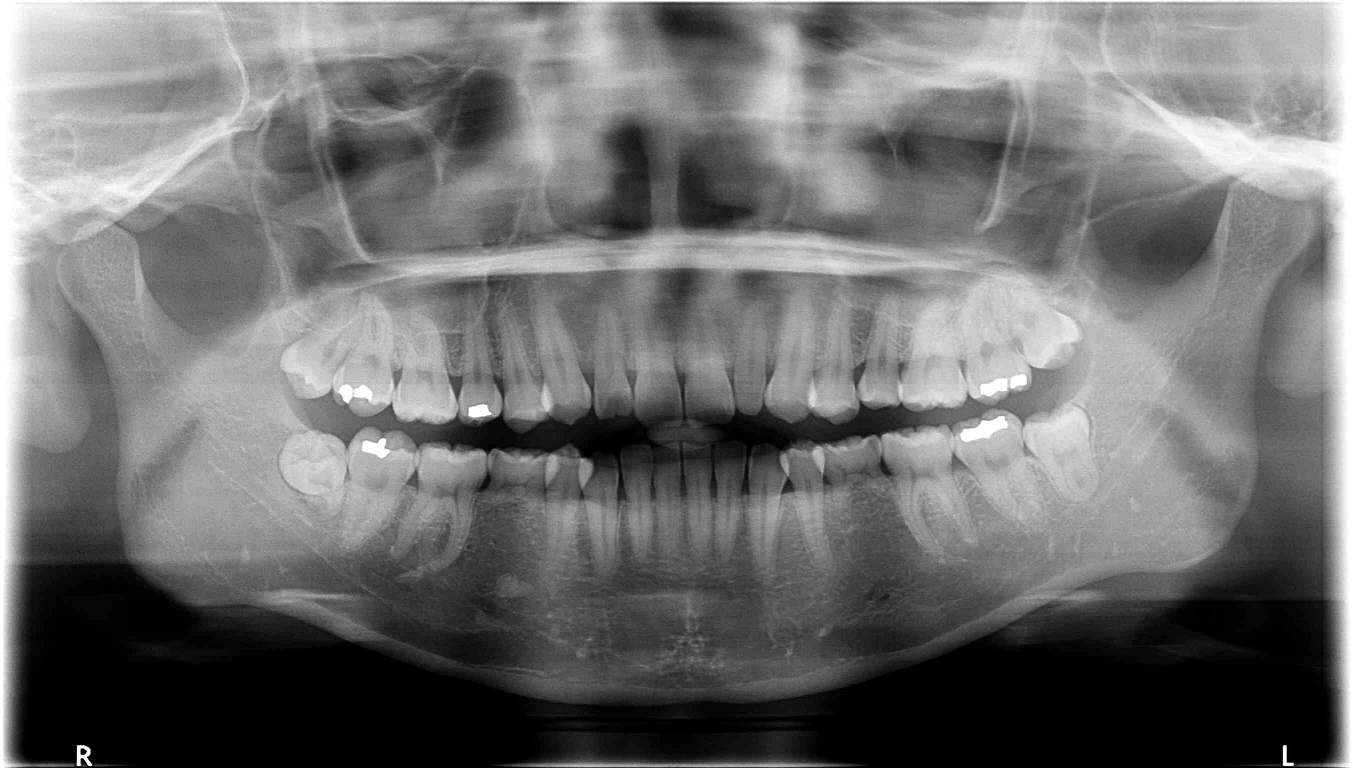

우선 저는 성인이구요(20대 후반) 사진에서 보이다시피 아래쪽에 유치가 두개 있는 상태입니다.

이걸 임플란트를 할지 교정으로 이를 밀어버릴지 고민이예요. 임플란트로만 처리한다면 더 오래 유치를 가지고 있어도 되겠지만... 입도 좀 튀어나온지라 어차피 이에 손을 대야 한다면 교정으로 돌출도 집어넣고 아래쪽 이도 교정을 할까 하거든요. (아래쪽 치열도 좀 삐뚤빼뚤해지고 있어요 ^^::)

윗니는 어차피 두개 발치하고 한다고 하시는데 아래쪽 유치가 가장 고민이네요. 조언좀 부탁드립니다 ^^ (사진 첨부했으니 함께 봐주시면 감사하겠습니다 ㅠㅠ)

네.. 고민이 많이 되겠군요. 교정치료시 발치된 공간은 앞니의 이동으로만 닫히는 것은 아니랍니다. 어금니의 디오이 같이 일어나면서 적당한 위치에 앞니를 당기게 되지요. 님의 경우는 아래는 유치를 제거하고 위의 작은 어금니를 발치하여 교정치료하는데 무리가 없어 보입니다. 자연치아로 치열을 형성하면서 님이 원하는 돌출된 입을 개선하는 효과까지 더해지는 부분으로 교정치료가 좋을 듯하내요...^^